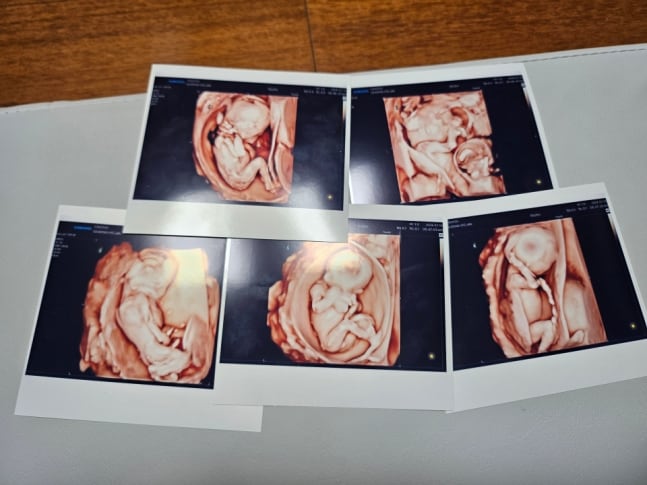

韓国初、自然妊娠で五つ子誕生…「世界的にも珍しい」(1/2)